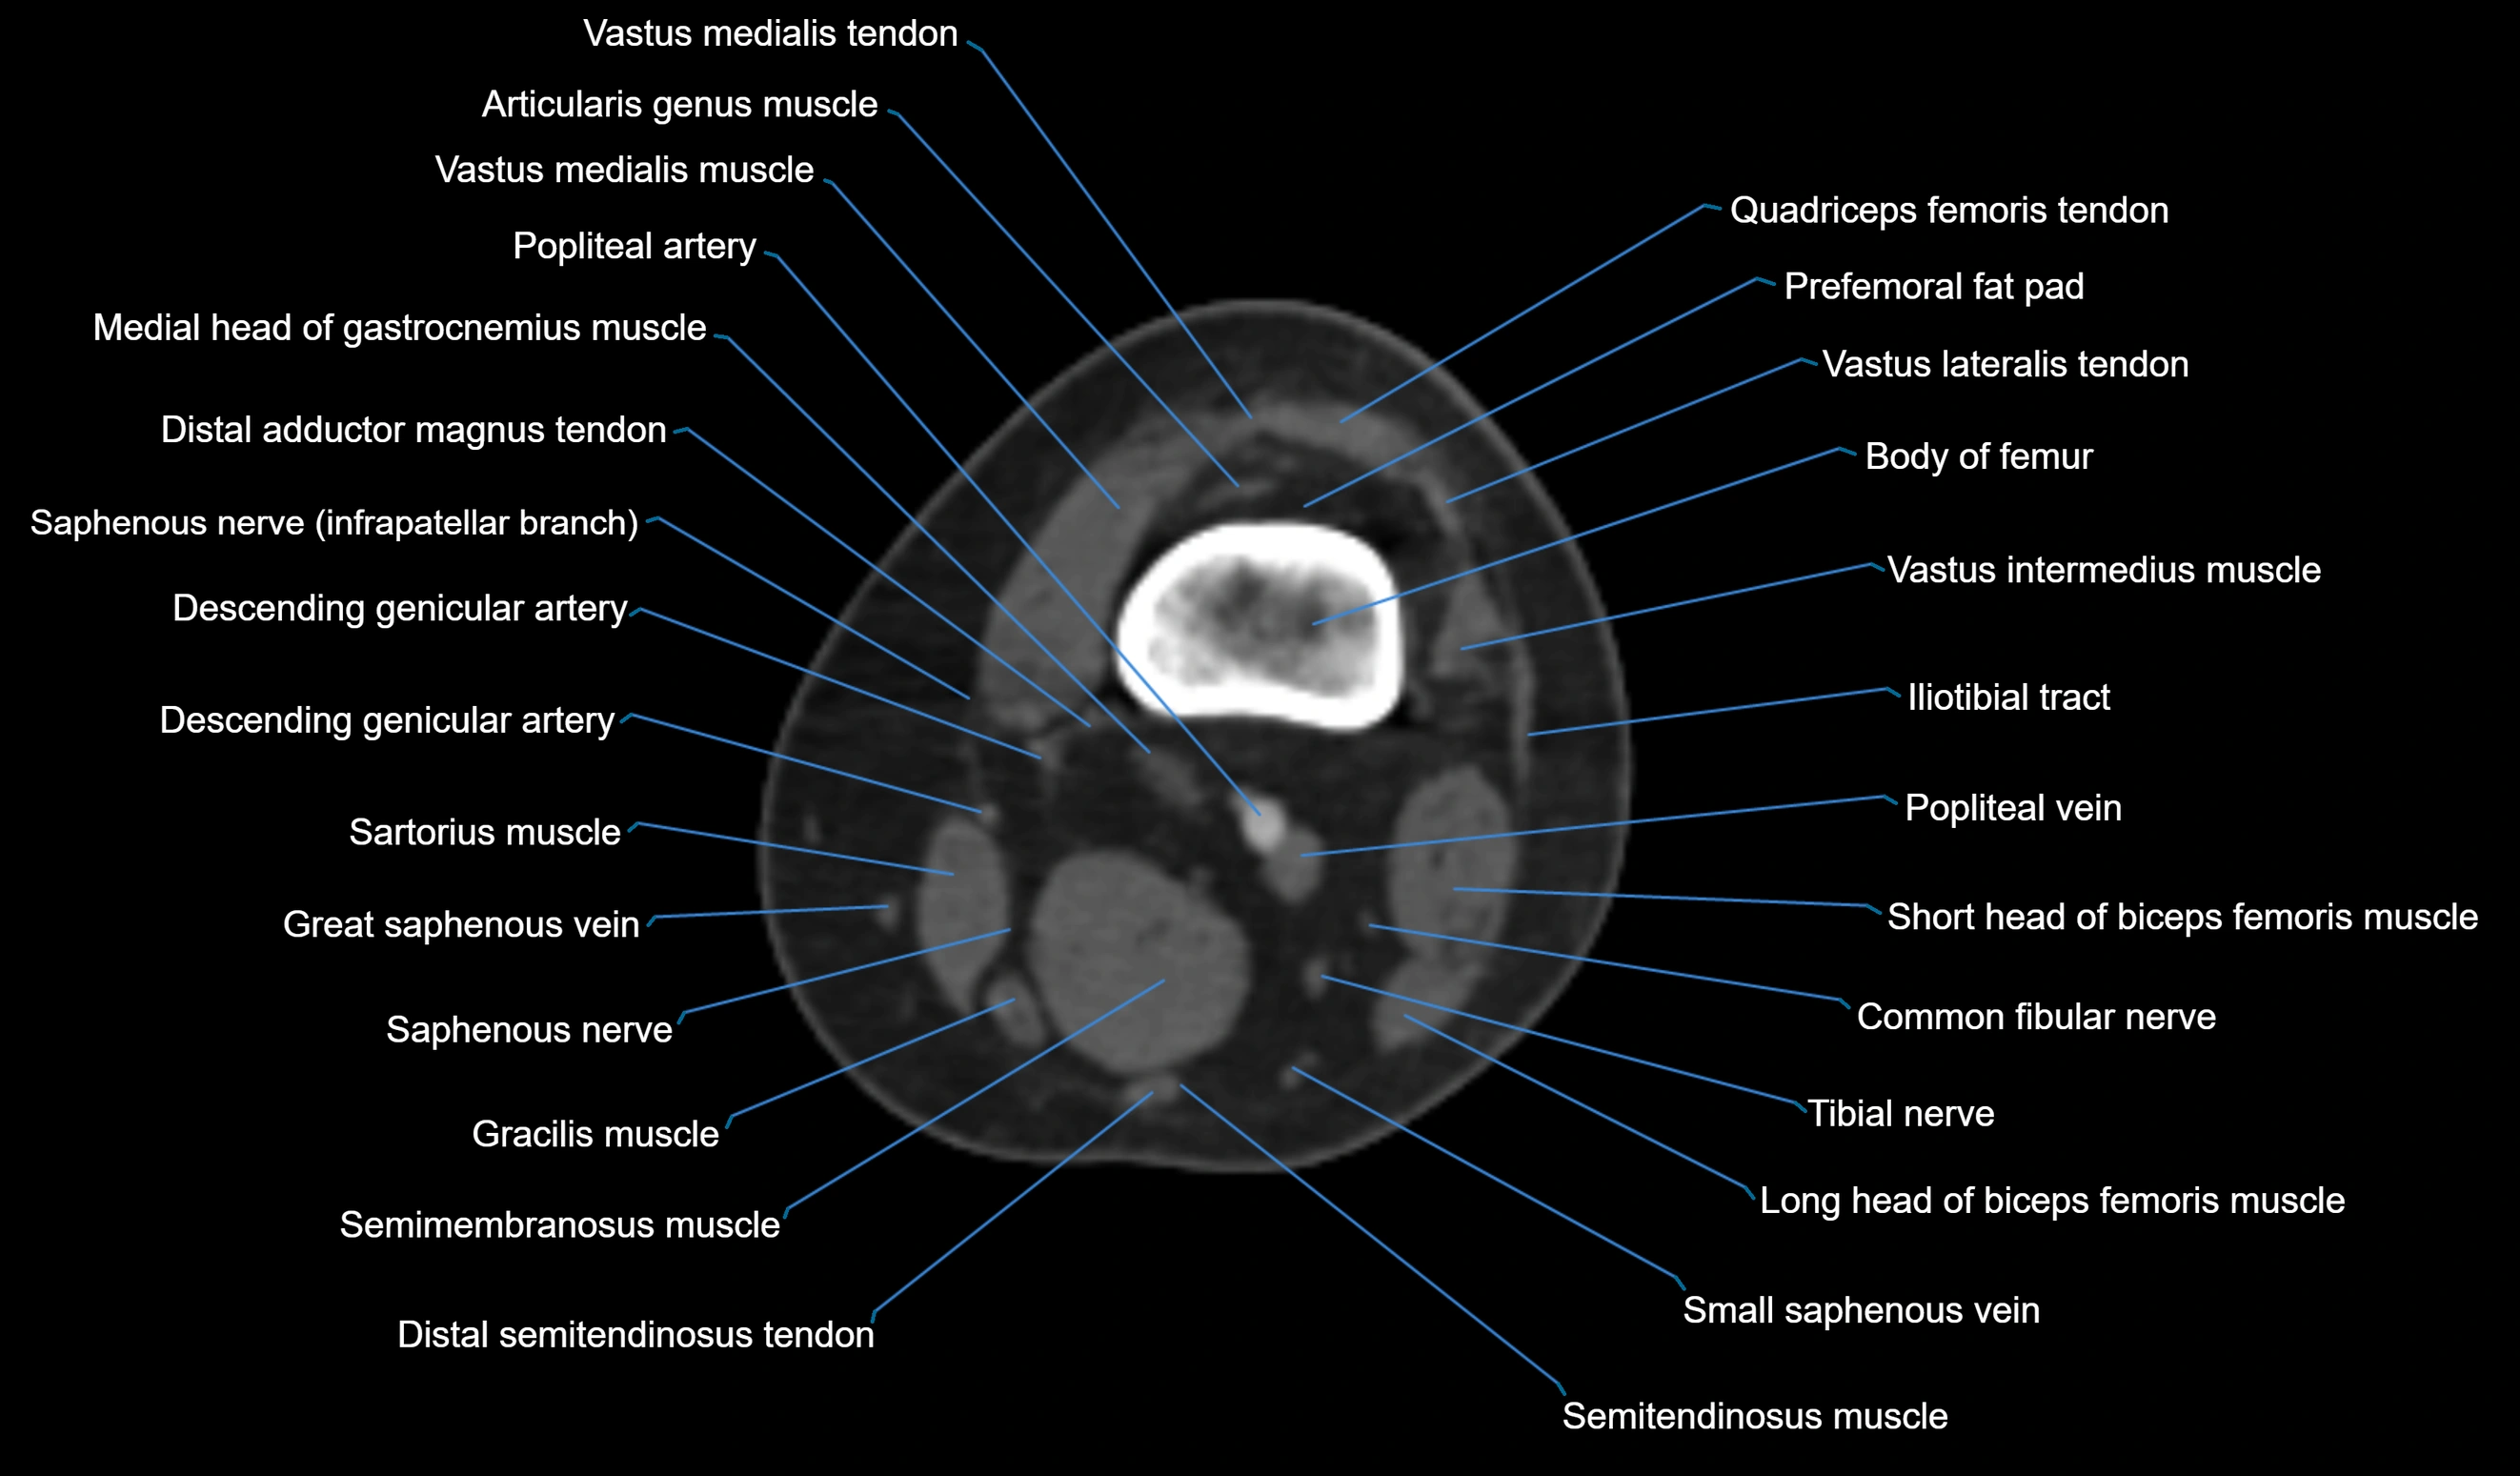

CT VRT 3D image

CT image